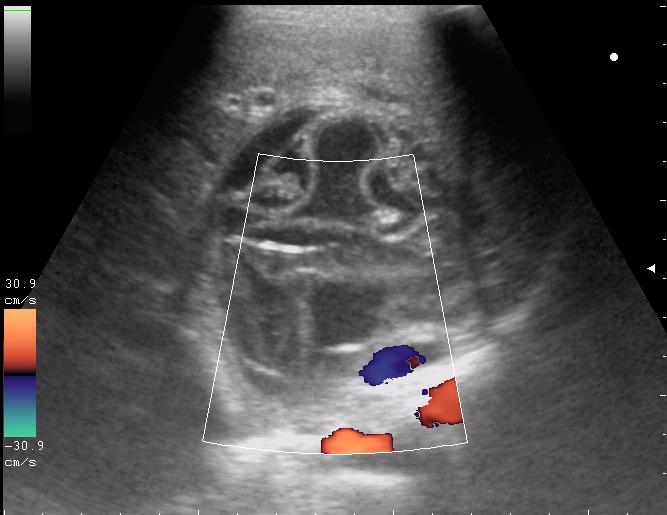

живой эхинококк.

Вложения

165.JPG